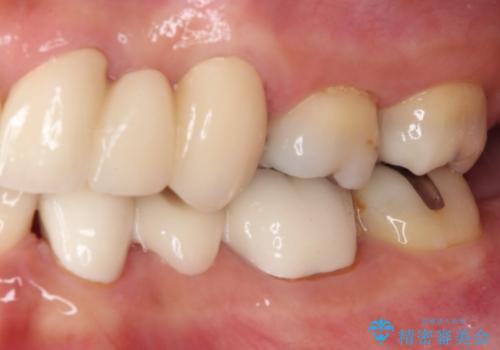

隙間が全て閉じたことで、長年食事の度に挟まる不快感が改善されました。

また、正面から見た印象がまるで自分の歯であるような自然な仕上がりとなりました。